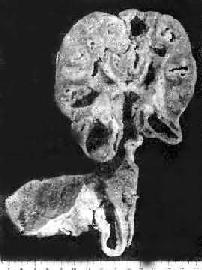

肾结核及输尿管结核

图18-15 肾结核及输尿管结核

肾实质内多数干酪样坏死灶及空洞形成;输尿管壁增厚,粘膜有多数结核结节及浅表溃疡形成

1.肾结核病 最常见于20~40岁。男性多于女性。多为单侧性、双侧性肾结核的发病率约为10%。病变开始于肾皮、髓质交界处或乳头体内。初为局灶性结核病变,病变继续扩大发展则发生干酪样坏死,破坏肾乳头而溃破入肾盂,成为结核性空洞。随着病变在肾内扩大蔓延,形成多数结核空洞,最后可使肾仅剩一空壳(图18-15)。由于液化的干酪样坏死物可随尿液下行,常使输尿管及膀胱感染。输尿管粘膜可发生溃疡和结核性肉芽组织形成,使管壁增厚、管腔狭窄,甚至阻塞,结果常引起肾盂积水或积脓。膀胱三角区往往最先受累,形成溃疡,以后可侵及整个膀胱,可引起膀胱壁纤维化,使膀胱容积缩小(膀胱挛缩)。膀胱的溃疡和纤维组织增生如影响到对侧的输尿管口,可使管口狭窄或失去正常的括约肌功能(关闭不全),造成对侧健肾引流不畅,最终可引起肾盂积水。结核菌也可逆行感染对侧肾。